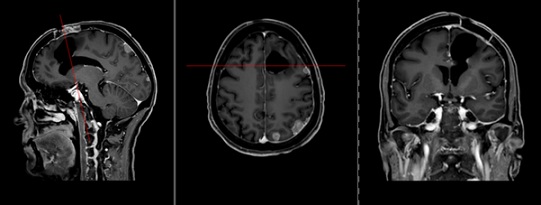

A 59-year-old female with LCNEC presented with progressive neurological symptoms, leading to a comprehensive re-evaluation. Initially, an intracranial cystic-necrotic metastasis in the left frontal lobe was identified (Figure 1), correlating with new-onset aphasia and confusion. Post-surgical analysis confirmed high-proliferation LCNEC, positive for synaptophysin, chromogranin A, CD56, and RB1 wild type. Primary lung involvement was evident in the right upper lobe. Despite cisplatin and etoposide-based radio-chemotherapy, extensive neurocranial and leptomeningeal carcinomatosis (LMC) developed (Figure 2). Whole-brain irradiation (10 x 3Gy) was administered as palliation. By October 2023, the patient experienced right dominant paraparesis, saddle hypesthesia, urinary incontinence, and weakened sphincter function. MRI revealed extensive intradural LMC, compressing the cauda equina at the L4/L5 level (Figure 3). Emergency radiotherapy (Th12-S1, 10 x 3Gy) was initiated, with extended coverage to C1-Th11. Initial improvement was noted; however, the patient's condition progressed to paraplegia.

Figure 1: T1-weighted MRI of the skull with contrast agent (sagittal, axial, and coronal views). The image reveals a cystic mass in the left frontal lobe, accompanied by a pronounced midline shift toward the opposite side.